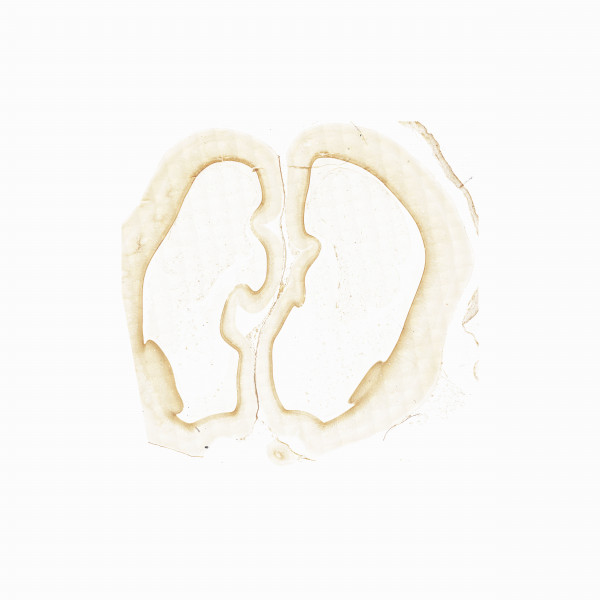

Human brain 13th gestational week

IHC 13th gw

Vimentin

Vimentin 36 25%

Vimentin 61 25%

Vimentin 81 25%

Vimentin 267 40%